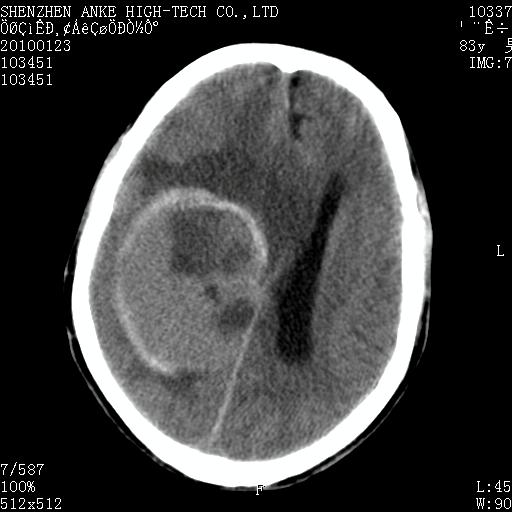

标题: CT24299:头颅平扫

患者:男,83岁,突发意思不清2天。原有脑梗塞病史。

肿瘤卒中,考虑恶性,依次淋巴瘤、转移瘤、恶性脑膜瘤、胶质母等,建议mri。

肿瘤卒中,考虑恶性脑膜瘤可能性大。

考虑脑膜瘤出血.

脑膜瘤多见于老年女性,与雌激素水平有关。本例虽为老年男性,但是本例还是考虑脑膜瘤的可能性大。

镰旁脑膜瘤卒中